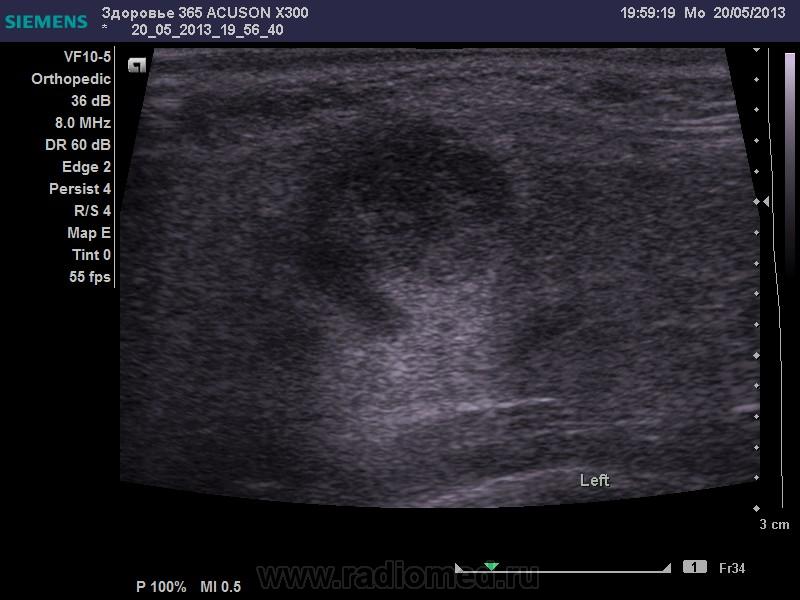

20.05.13. УЗИ мягких тканей. Лимфаденит.

Молодая женщина пришла на обследования из-за болезненности в области шеи в подчелюстном треугольнике.

Слева в области подчелюстного треугольника определяется образование шаровидной формы диаметром оси 14 мм с внутренней гипоэхогенной структурой.

При ЦДК аваскулярно.

Данная УЗИ-картина может соответствовать лимфадениту левого подчелюстного узла.

Не пойму, что вокруг образования, клетчатка, или железистая ткань. Да и лимфоузел будет полностью аваскулярным... даже не знаю, когда. При гнойном расплавлении и тромбозе сосудов ворот.

Если это лимфатический узел, то почему он аваскулярен? Может быть киста шейная?И опять же видео, не будет лишним.

Наличие тостой капсулы и дорсального усиления больше говорят о жидкостной природе. Я за кисту.